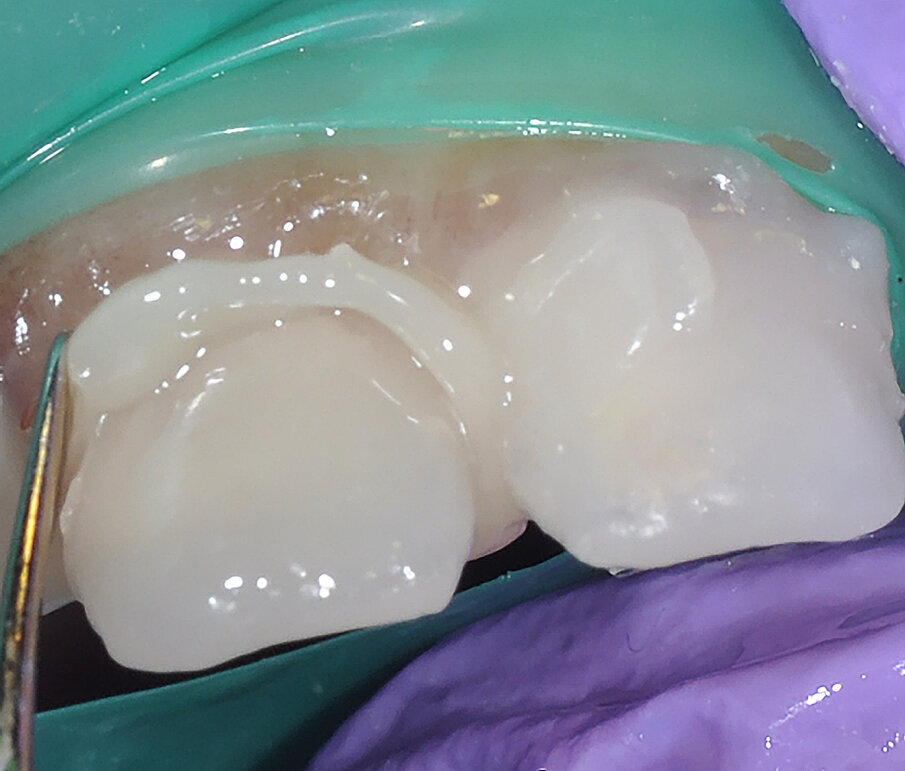

All caries was removed using a round diamond bur, and mesial and distal reduction were achieved with a fine tapered diamond bur to open the interproximal contacts and to begin circumferential reduction. Buccal and lingual reduction were achieved with a round-ended straight fissure diamond point. All margins and the extent of reduction were dictated by the caries and kept to a minimum in order to preserve as much tooth structure as possible. The margins were kept supragingival (Fig. 4).

Fig. 4: Crown preparations with margins kept supra-gingival.